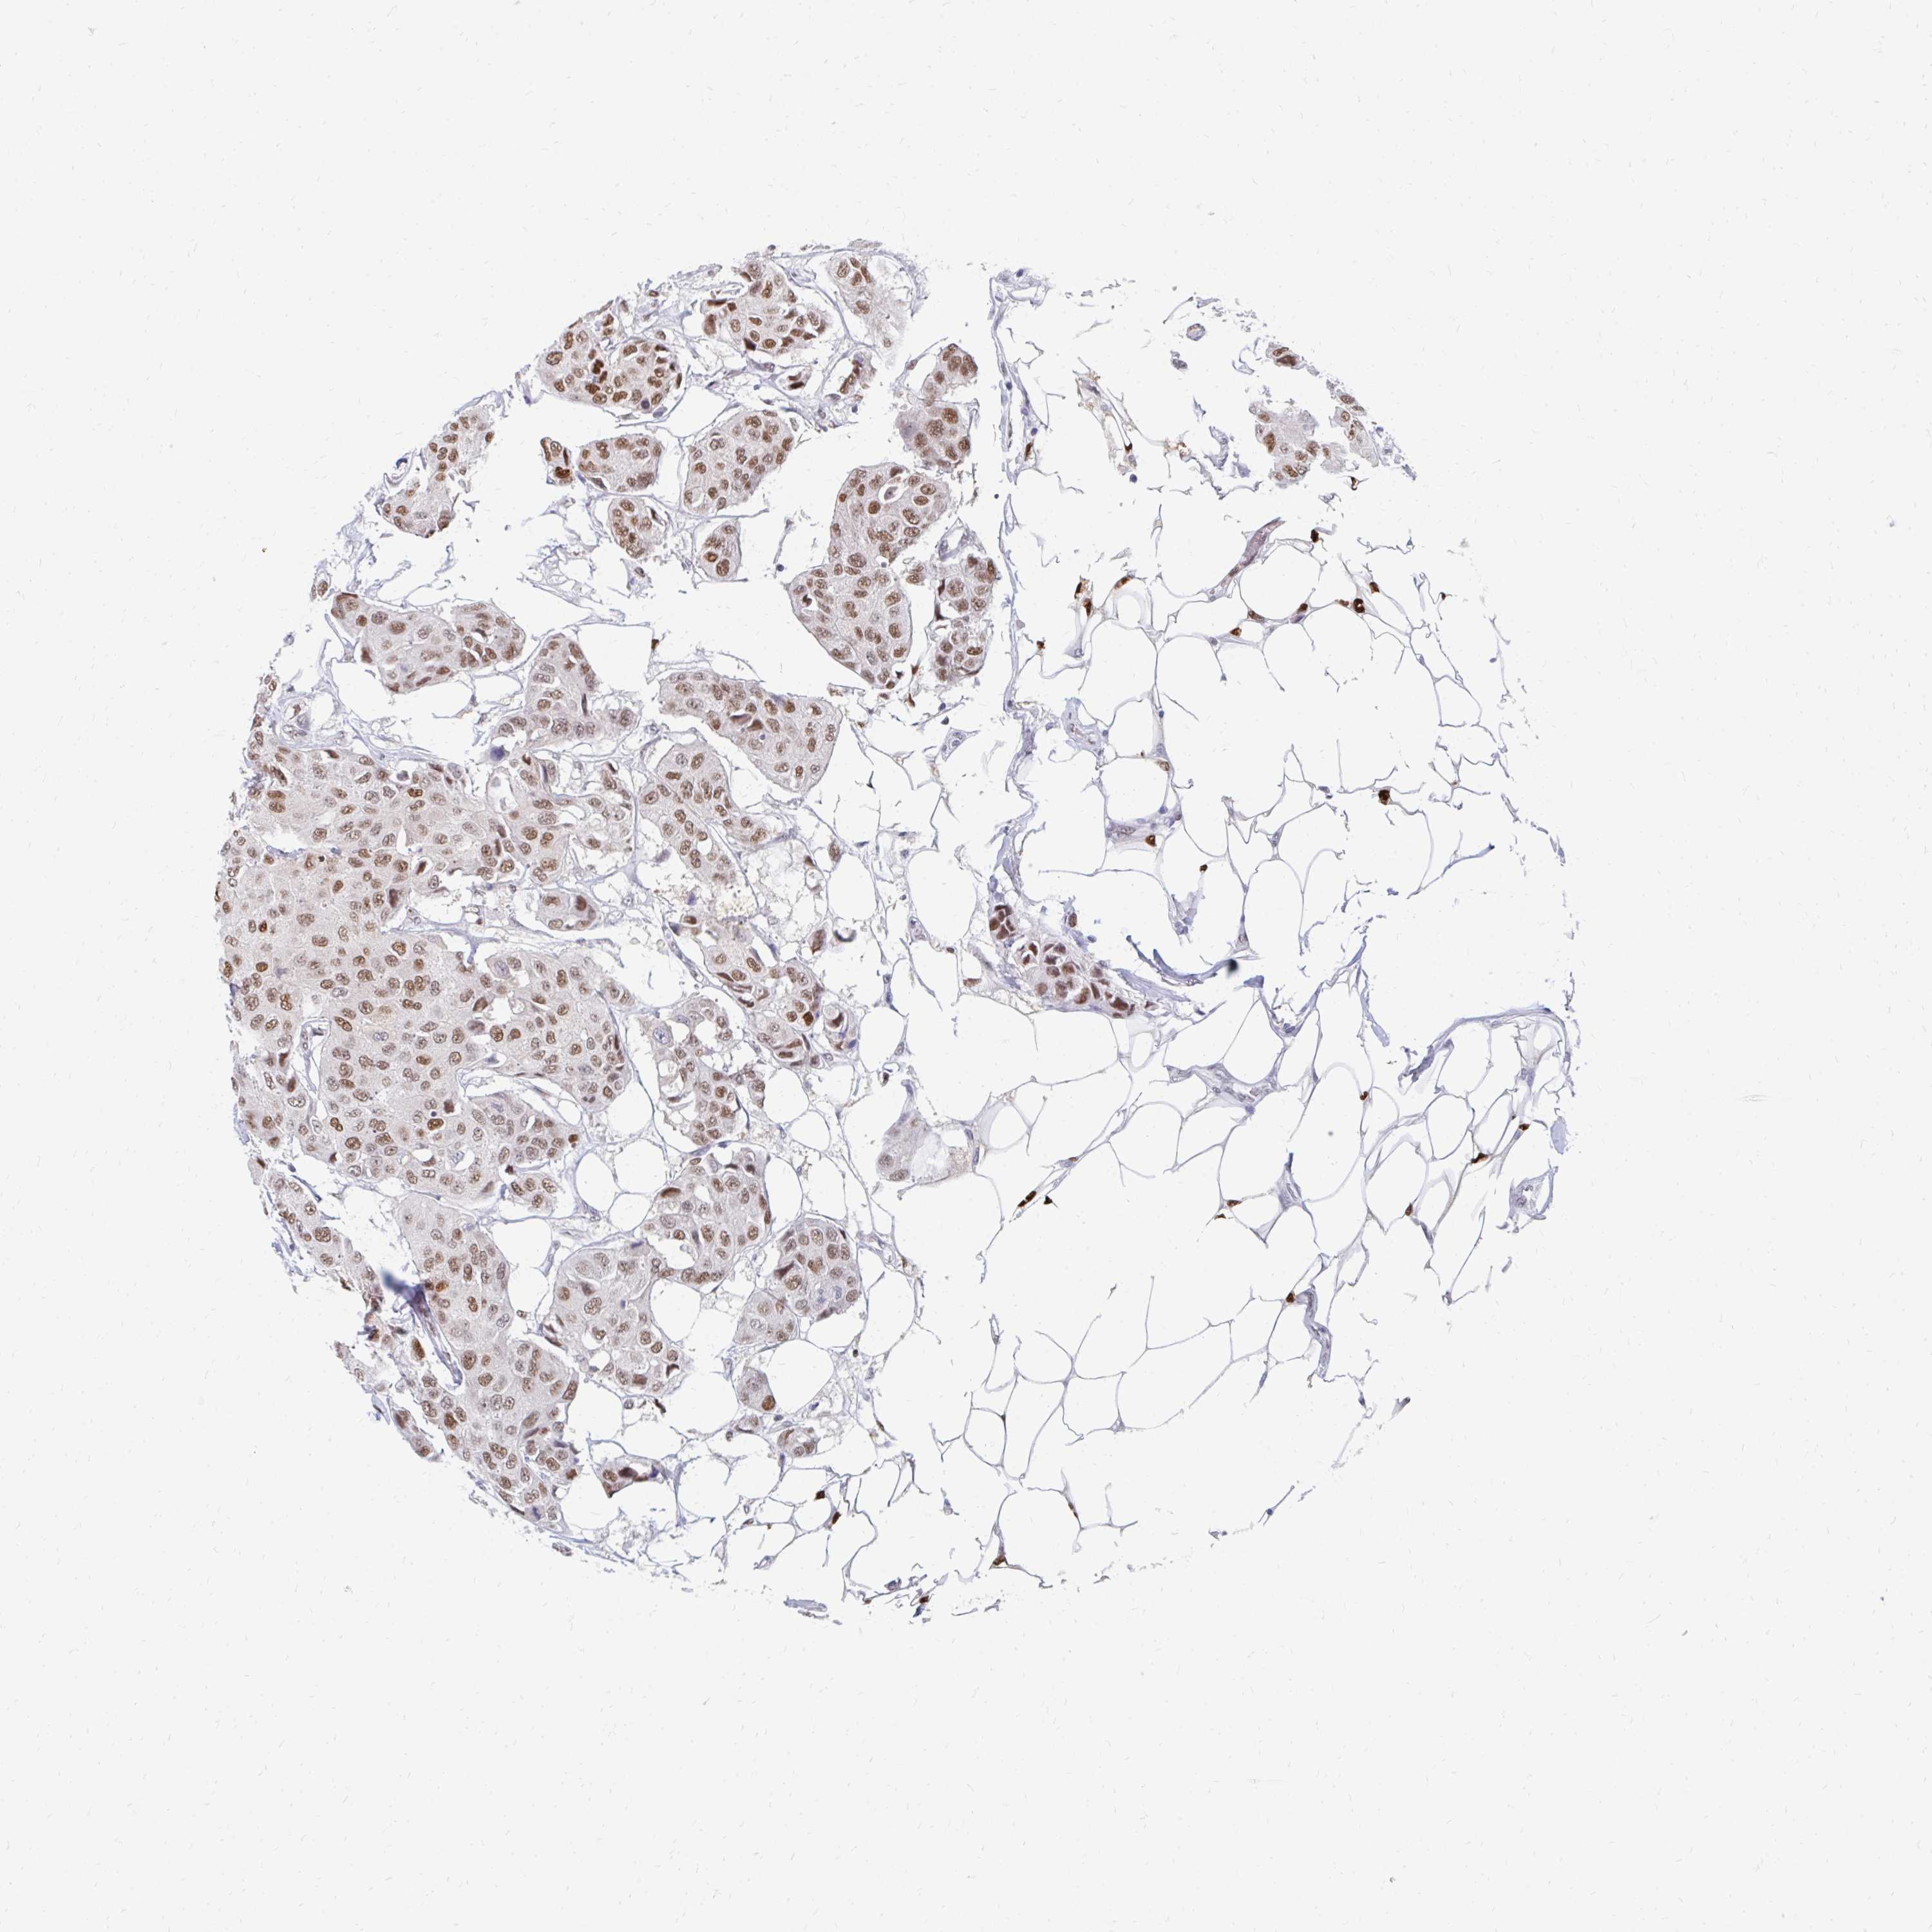

CANCER BREAST CANCER Show tissue menu

BRCA TCGA BRCA VALIDATION PROTEIN EXPRESSION

Breast cancer

Human cancer

Breast invasive carcinoma